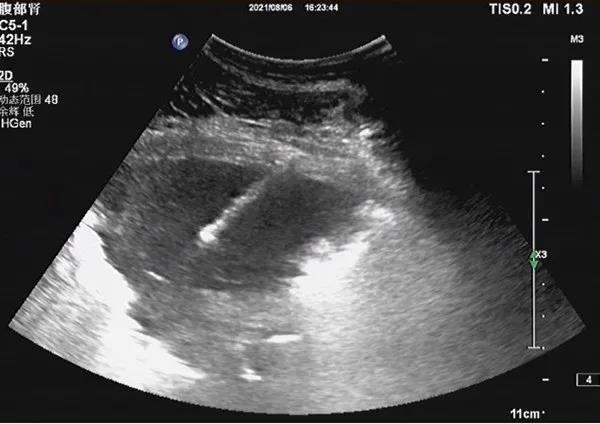

8月6日下午,陈老太在超声诊室行超声引导下行肺穿刺活检术,术前超声提示右上肺可见范围约76*42mm低回声区,边界清,形态不规则,CDFI可见短条状血流信号。超声科朱昊主任、谈卫杰主任在行超声扫查后,选取了合适的进针路径,于右腋中线进行超声引导,利用全自动活检枪成功取出一条长约33mm的组织,穿刺成功!